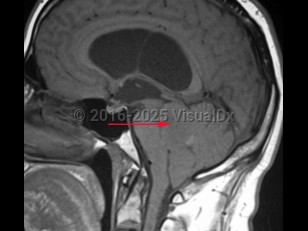

Ependymoma

An ependymoma is a tumor of the brain or spinal cord arising from ependymal cells. Ependymomas account for 4% of central nervous system (CNS) tumors in adults and 10% of CNS tumors in children. In children, they are most often located in the 4th ventricle and posterior fossa, whereas in adults, they are more frequently located in the spinal cord. In the spinal cord, they tend to occur centrally, causing symmetric cord expansion. Peak incidence in adults occurs between 30 and 40 years of age.

Signs and symptoms depend on tumor location but may include headache, vomiting, papilledema, lethargy, ataxia, nystagmus, weakness or difficultly walking, sensory disturbance, urinary or bowel dysfunction. Ependymomas have a high incidence in patients with neurofibromatosis type 2.